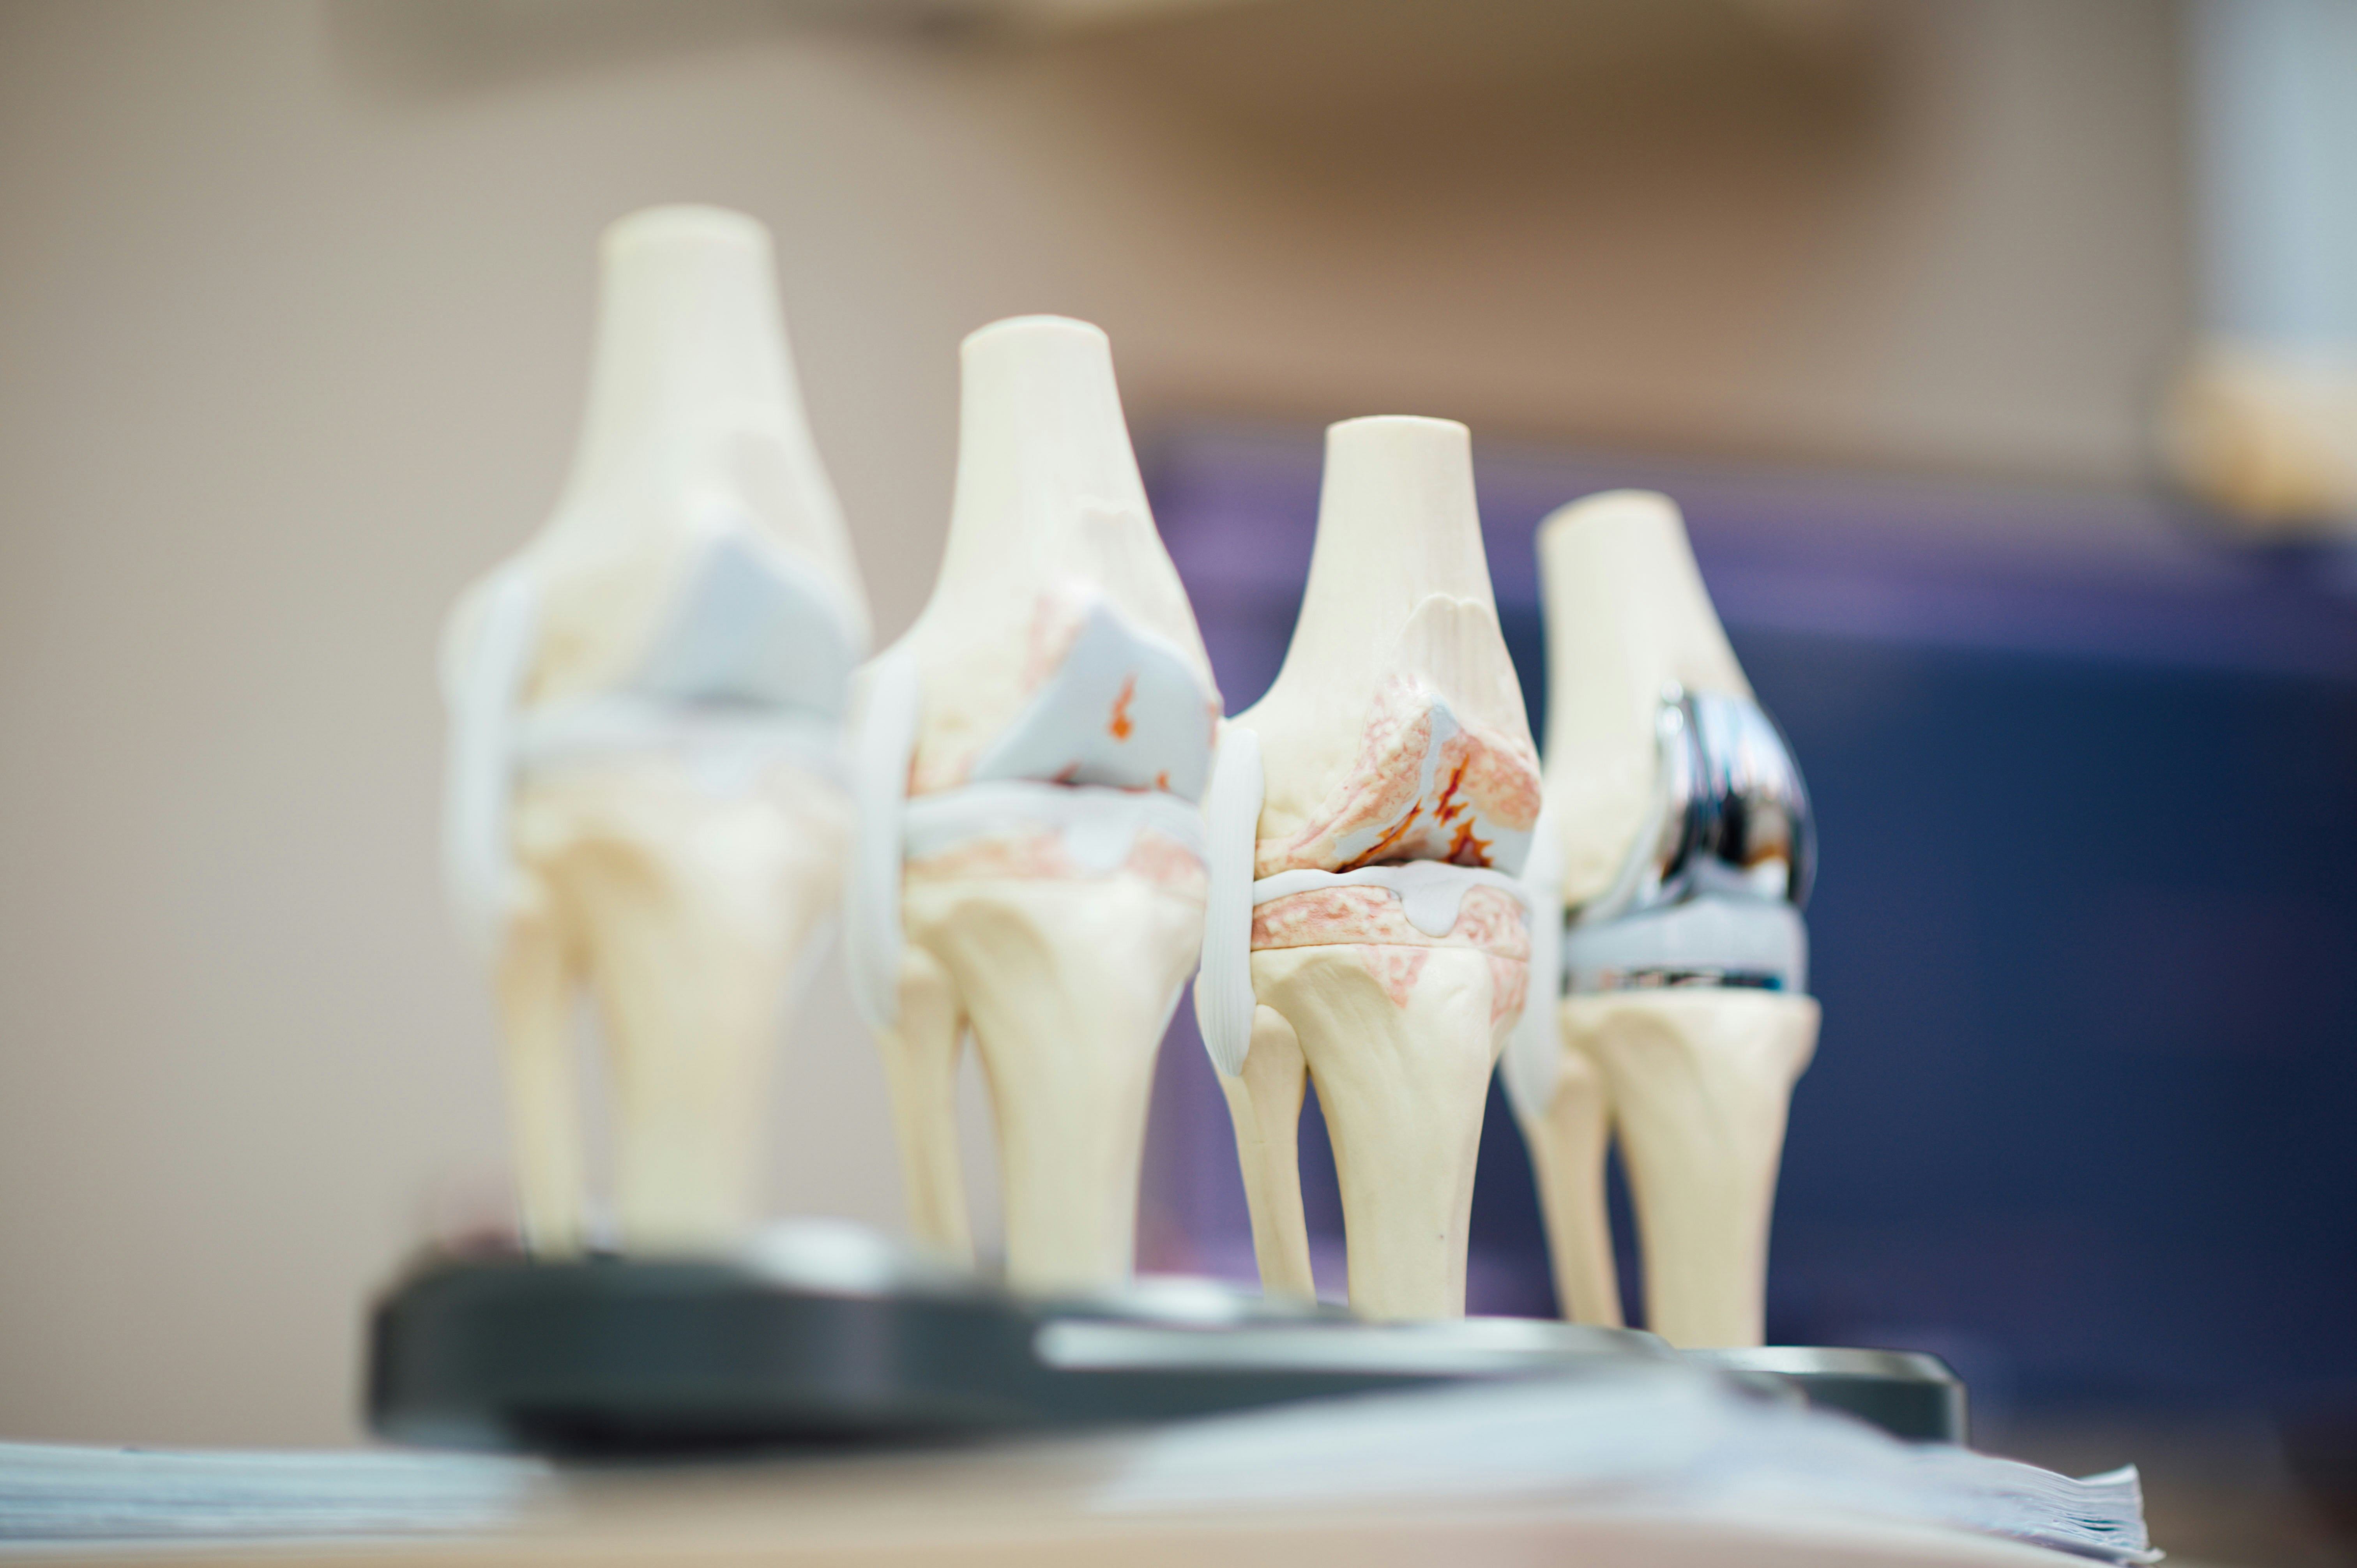

| 말기 (중증) | 가만히 있어도 통증, 관절 변형 | 인공관절 치환술 고려, 집중 재활 | 가벼운 관절 가동 범위 스트레칭 |